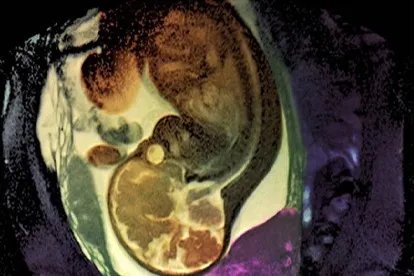

葡萄胎症状图

葡萄胎图早期症状1.停经后阴道流血如果女性患有葡萄胎,在停经8-12周左右,可能会出现不规则的阴道流血,血液颜色多呈深褐色、鲜红色等颜色。2.呕吐体内存在葡萄胎的女性通常会较早出现妊娠呕吐,并且该症状持续的时间比较长,严重时可能导致女性脱水。3.腹痛女性下腹部多有阵发性疼痛感,但通常能忍受。如果出现了卵巢黄素化囊肿扭转或破裂的情况,可能引起急性腹痛。疾病原因染色体比例异常可能导致葡萄胎出现,而缺乏维生素A、高龄生育、既往流产史、月经不规则等因素也可能诱发葡萄胎。治疗方案在确诊后,女性需及时行清宫手术进行治疗,以免病情进一步发展。如果葡萄胎存在恶性倾向,或人绒毛膜促性腺激素未见进行性下降,女性还需要遵医嘱使用甲氨蝶呤片、注射用放线菌素D、复方氟尿嘧啶口服溶液等药物进行预防性化疗。